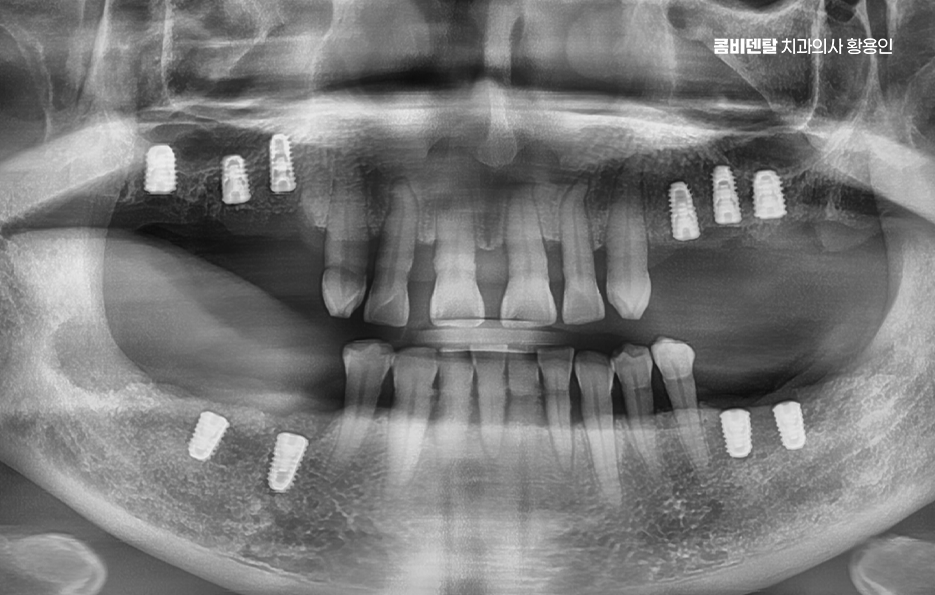

그렇다면 어금니 발치 후, 임플란트를 잘 받기 위한 방법은 뭐냐 하면 첫 번째는 시기를 놓치지 않는 것인데 발치 후 3개월 내에는 임플란트를 심는 게 이상적이며 사실 요즘은 경우에 따라 ‘즉시 식립’이라고 해서 발치 당일에 임플란트를 심는 경우도 많아지고 있기 때문에 발치와 함께 임플란트 치료 계획을 세우는 것이 이상적이라 할 수 있어요

나에게 맞는 치료를 하기 위해서는 정확한 진단과 설계가 중요하며 CT 촬영 등을 통해 신경 위치, 뼈의 양, 두께 등을 정밀하게 진단한 다음, 교합과 치열 구조에 맞는 위치에 임플란트를 심는 게 중요한데 잘못된 위치에 심어지면 오래 쓰기 어렵고, 나중에 통증이나 염증이 생길 수 있었어요.

임플란트는 처음 수술보다 이후 관리가 더 중요하다고 할 정도니까, 처음부터 잘 설계된 치료계획 아래 수술을 받는 게 중요하며 그 이후로도 사후관리를 잘하는 것이 곧 임플란트의 수명 유지에 중요한 거예요

임플란트는 자연치처럼 충치가 생기진 않지만, 임플란트 주위염이라는 문제가 생길 수 있으며 자연치의 치주염처럼 뼈가 녹고 잇몸이 붓는 염증인데 방치하면 결국 임플란트가 흔들리고 탈락하게 되서 정기적인 스케일링과 함께 정해진 시기에 치과에서 검진을 받아야 하고 양치나 치간칫솔, 워터픽 같은 도구로 관리도 꾸준히 해줘야 하며 치료 계획부터 유지까지 장기적인 관점에서 치료를 바라봐야 하기 때문에 치과 역시도 오래 함께할 곳을 잘 따져보시길 바라고 있어요